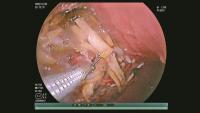

女童发烧17天脑子竟被啃出十几个洞 烟曲霉菌成元凶

女童发烧17天脑子竟被啃出十几个洞

6岁女童发烧17天意识不清,脑子竟被“啃”出十几个洞 烟曲霉菌作祟

6岁女童发烧17天意识不清,脑子竟被啃出十几个洞